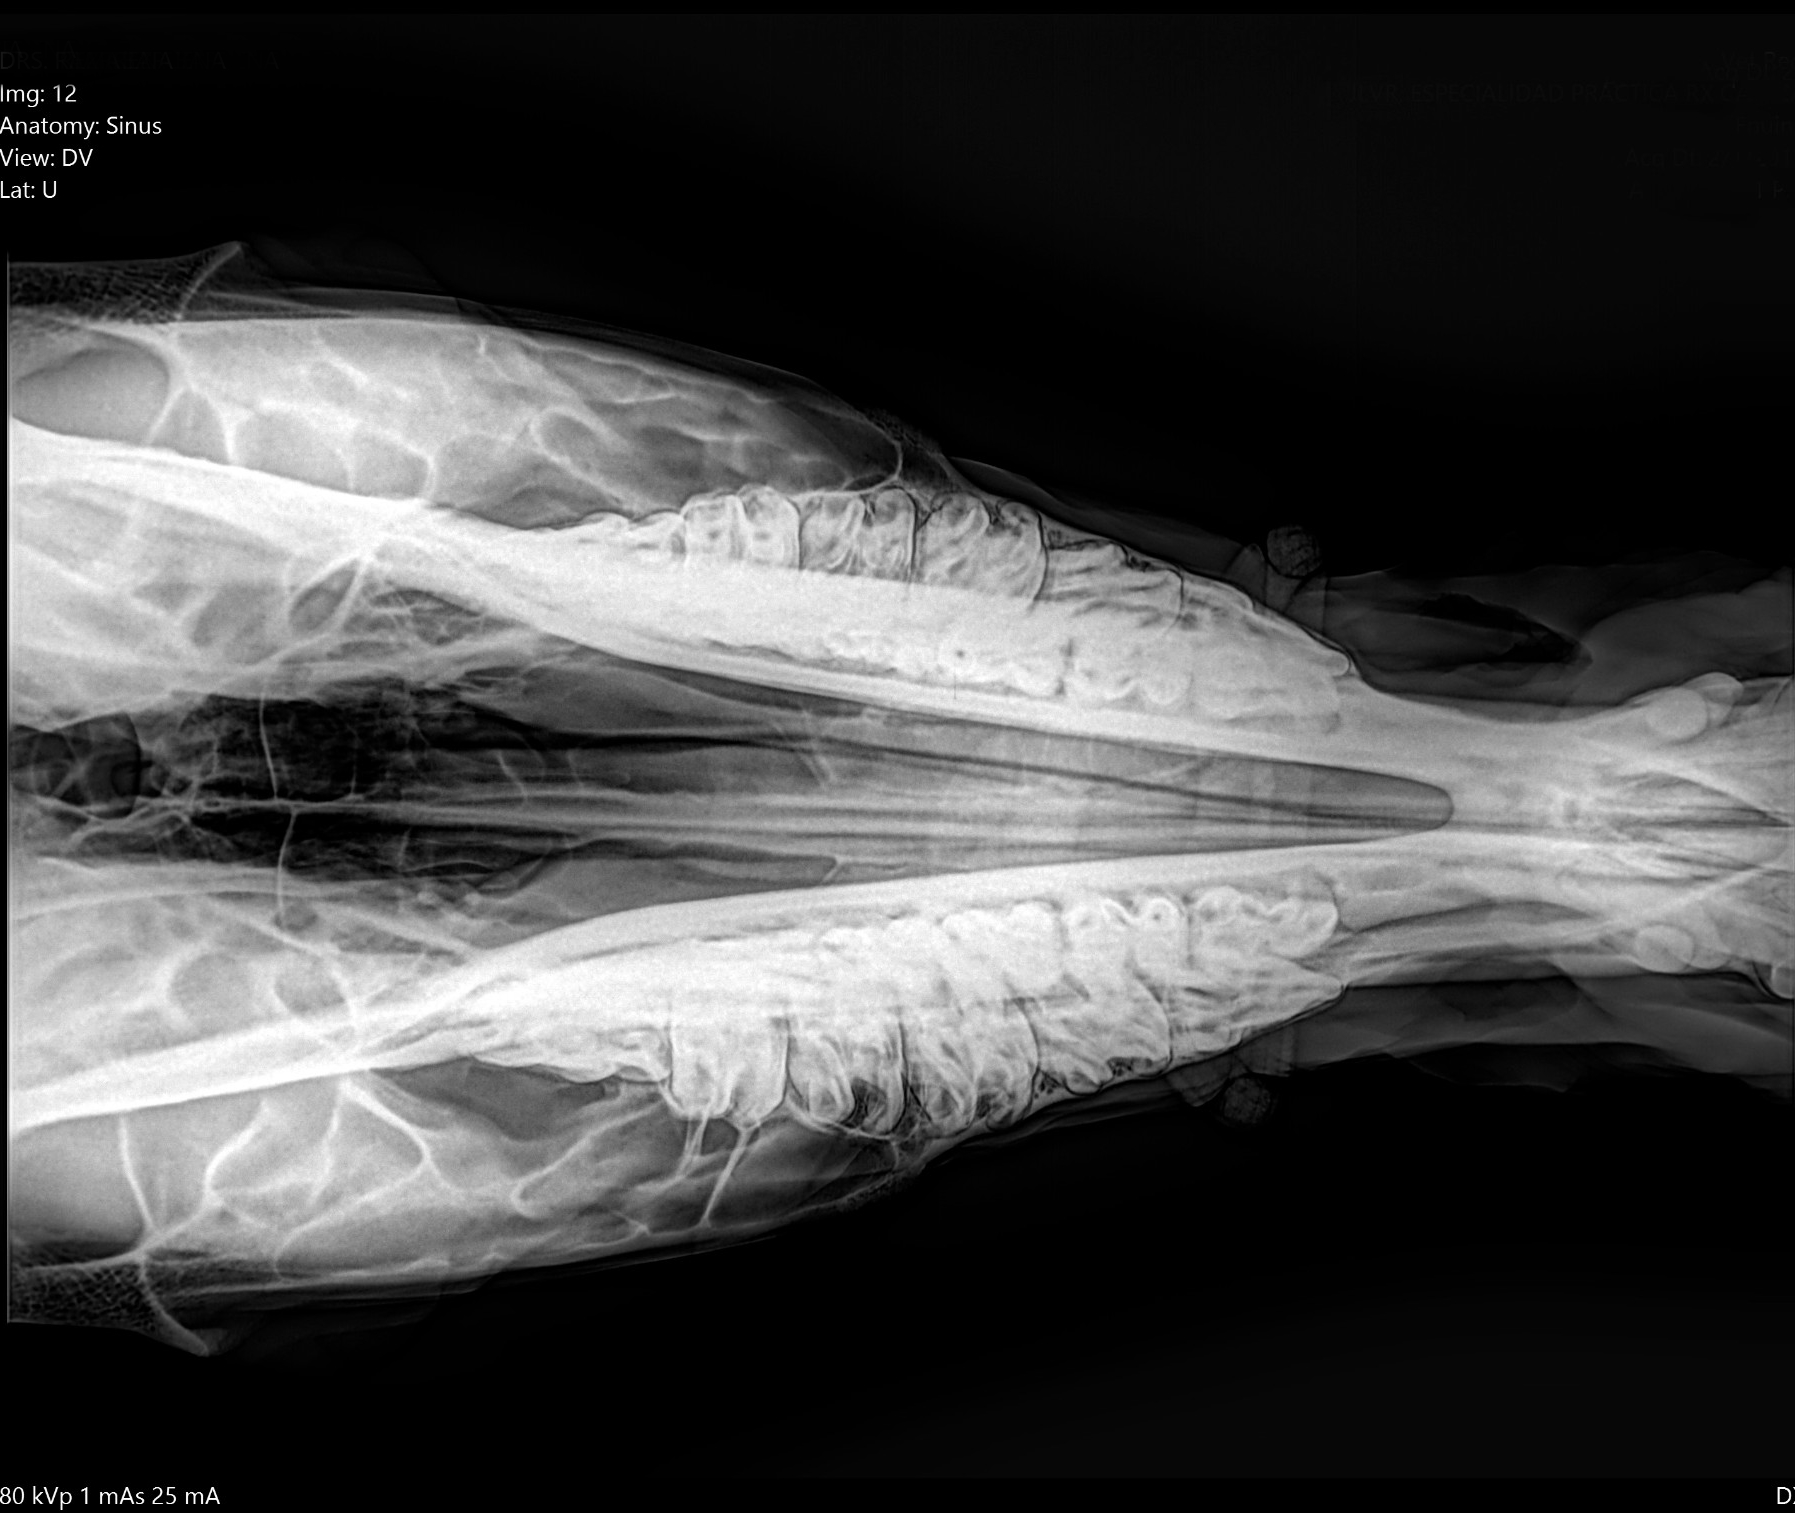

THE GENUS RHYNCHOTERIUM (MAMMALIA-PROBOSCIDEA) in the Hemphilliam - Blancan (NALMA) of central Mexico

In research in Neogene deposits from central Mexico, have collected abundant fossil materials, that have been referred to Rhynchotherium, based in not diagnostic materials and inaccurate age and locality, that not adequately di erentiate between the genus Rhynchotherium, Cuvieronius and Gomphotherium (Lucas y Morgan 2008).